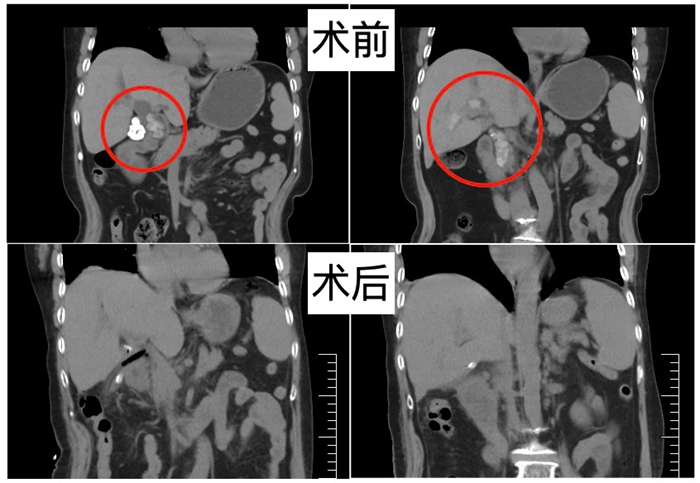

近日,北京天坛医院普外科副主任俞巍团队成功运用荧光腹腔镜联合电子胆道镜的微创技术,为一位复杂胆道结石患者进行了精准取石手术。手术完整切除已经硬化的胆囊,且不仅取净了肝外胆管铸型的大结石,更是一次性取净深达二三级肝内胆管多个分支的结石。仅用4个0.5~1cm的微小切口,患者术后很快恢复饮食,复查 CT 显示结石已完全清除,标志着医院在复杂胆道结石微创治疗领域的重要突破。

“如何一次性取净结石,同时最大程度减小患者的手术创伤,是我们团队面临的最大难题。” 俞巍介绍,针对患者病情,团队摒弃传统开腹方案,尝试利用现在先进的荧光腹腔镜联合电子胆道镜,通过微创的方式取石。手术中,首先通过荧光腹腔镜的显影导航功能,精准定位胆道位置,为手术解剖提供清晰指引。随后在腹腔镜视野下微创打开胆管,再将电子胆道镜置入,以 “镜中镜” 的形式,精准锁定结石位置,通过专用网篮将所有结石完整取出。术后,患者腹部只遗留四个0.5-1cm的切口,手术后患者很快恢复了饮食,复查腹部CT肝内外结石已经全部取净。整个手术过程创伤小、视野清、取石准,实现了 “微创化” 与 “根治性” 的双重目标。